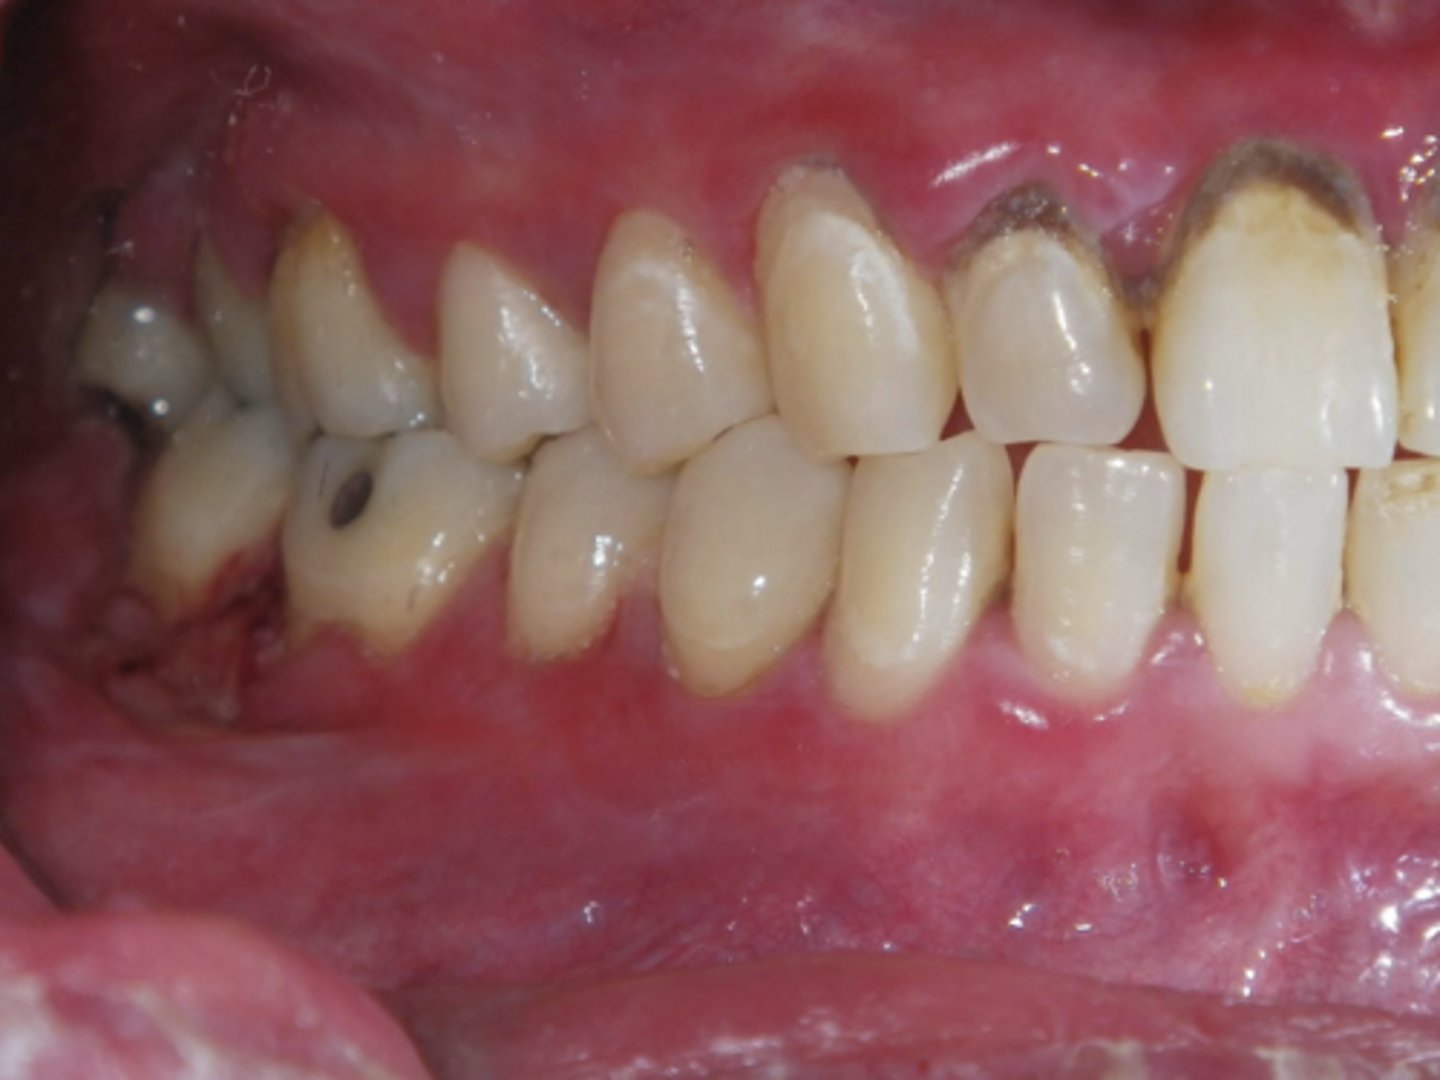

What condition?

lichen planus (reticular)